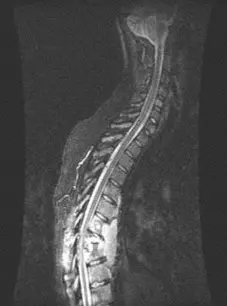

Computerized Tomography:

- Further delineate bony destruction and sequestrum Magnetic Resonance Imaging with Contrast:

- Soft tissue mass, abscess

- Nerve root, cord status

- Distant abscess

- Non-enhanced cold abscess with enhanced peripheral ring